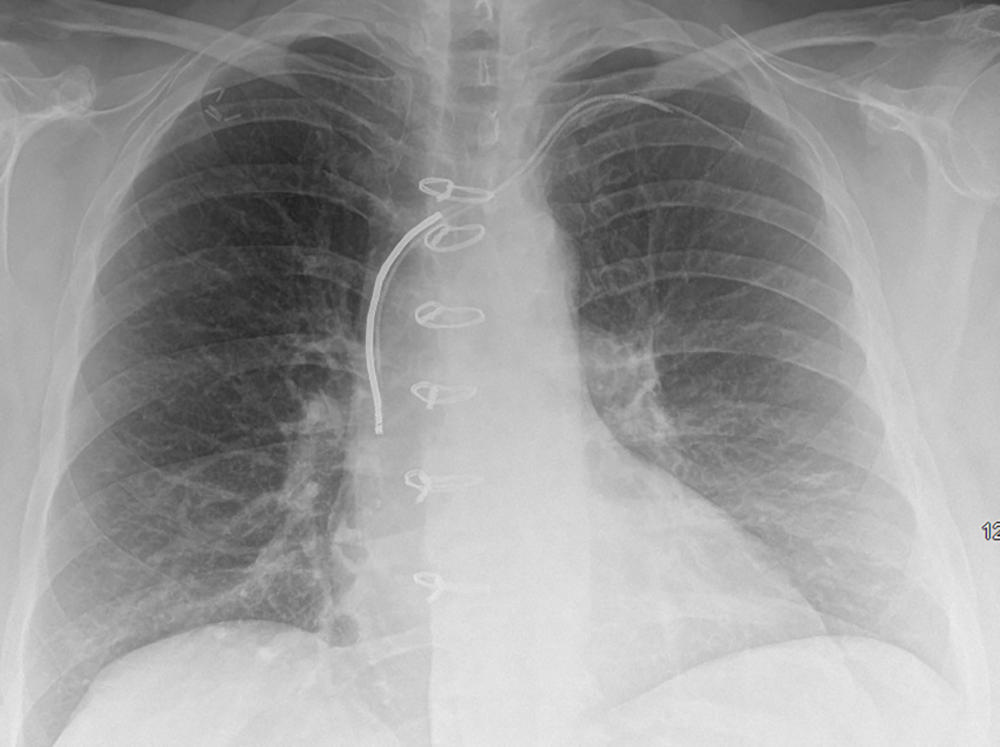

Figure 6. Chest radiograph, posteroanterior view, in an 85-year-old woman with history of previous pacemaker that was explanted and retained right ventricular pacing lead. There is evidence of vertebroplasties at multiple levels.